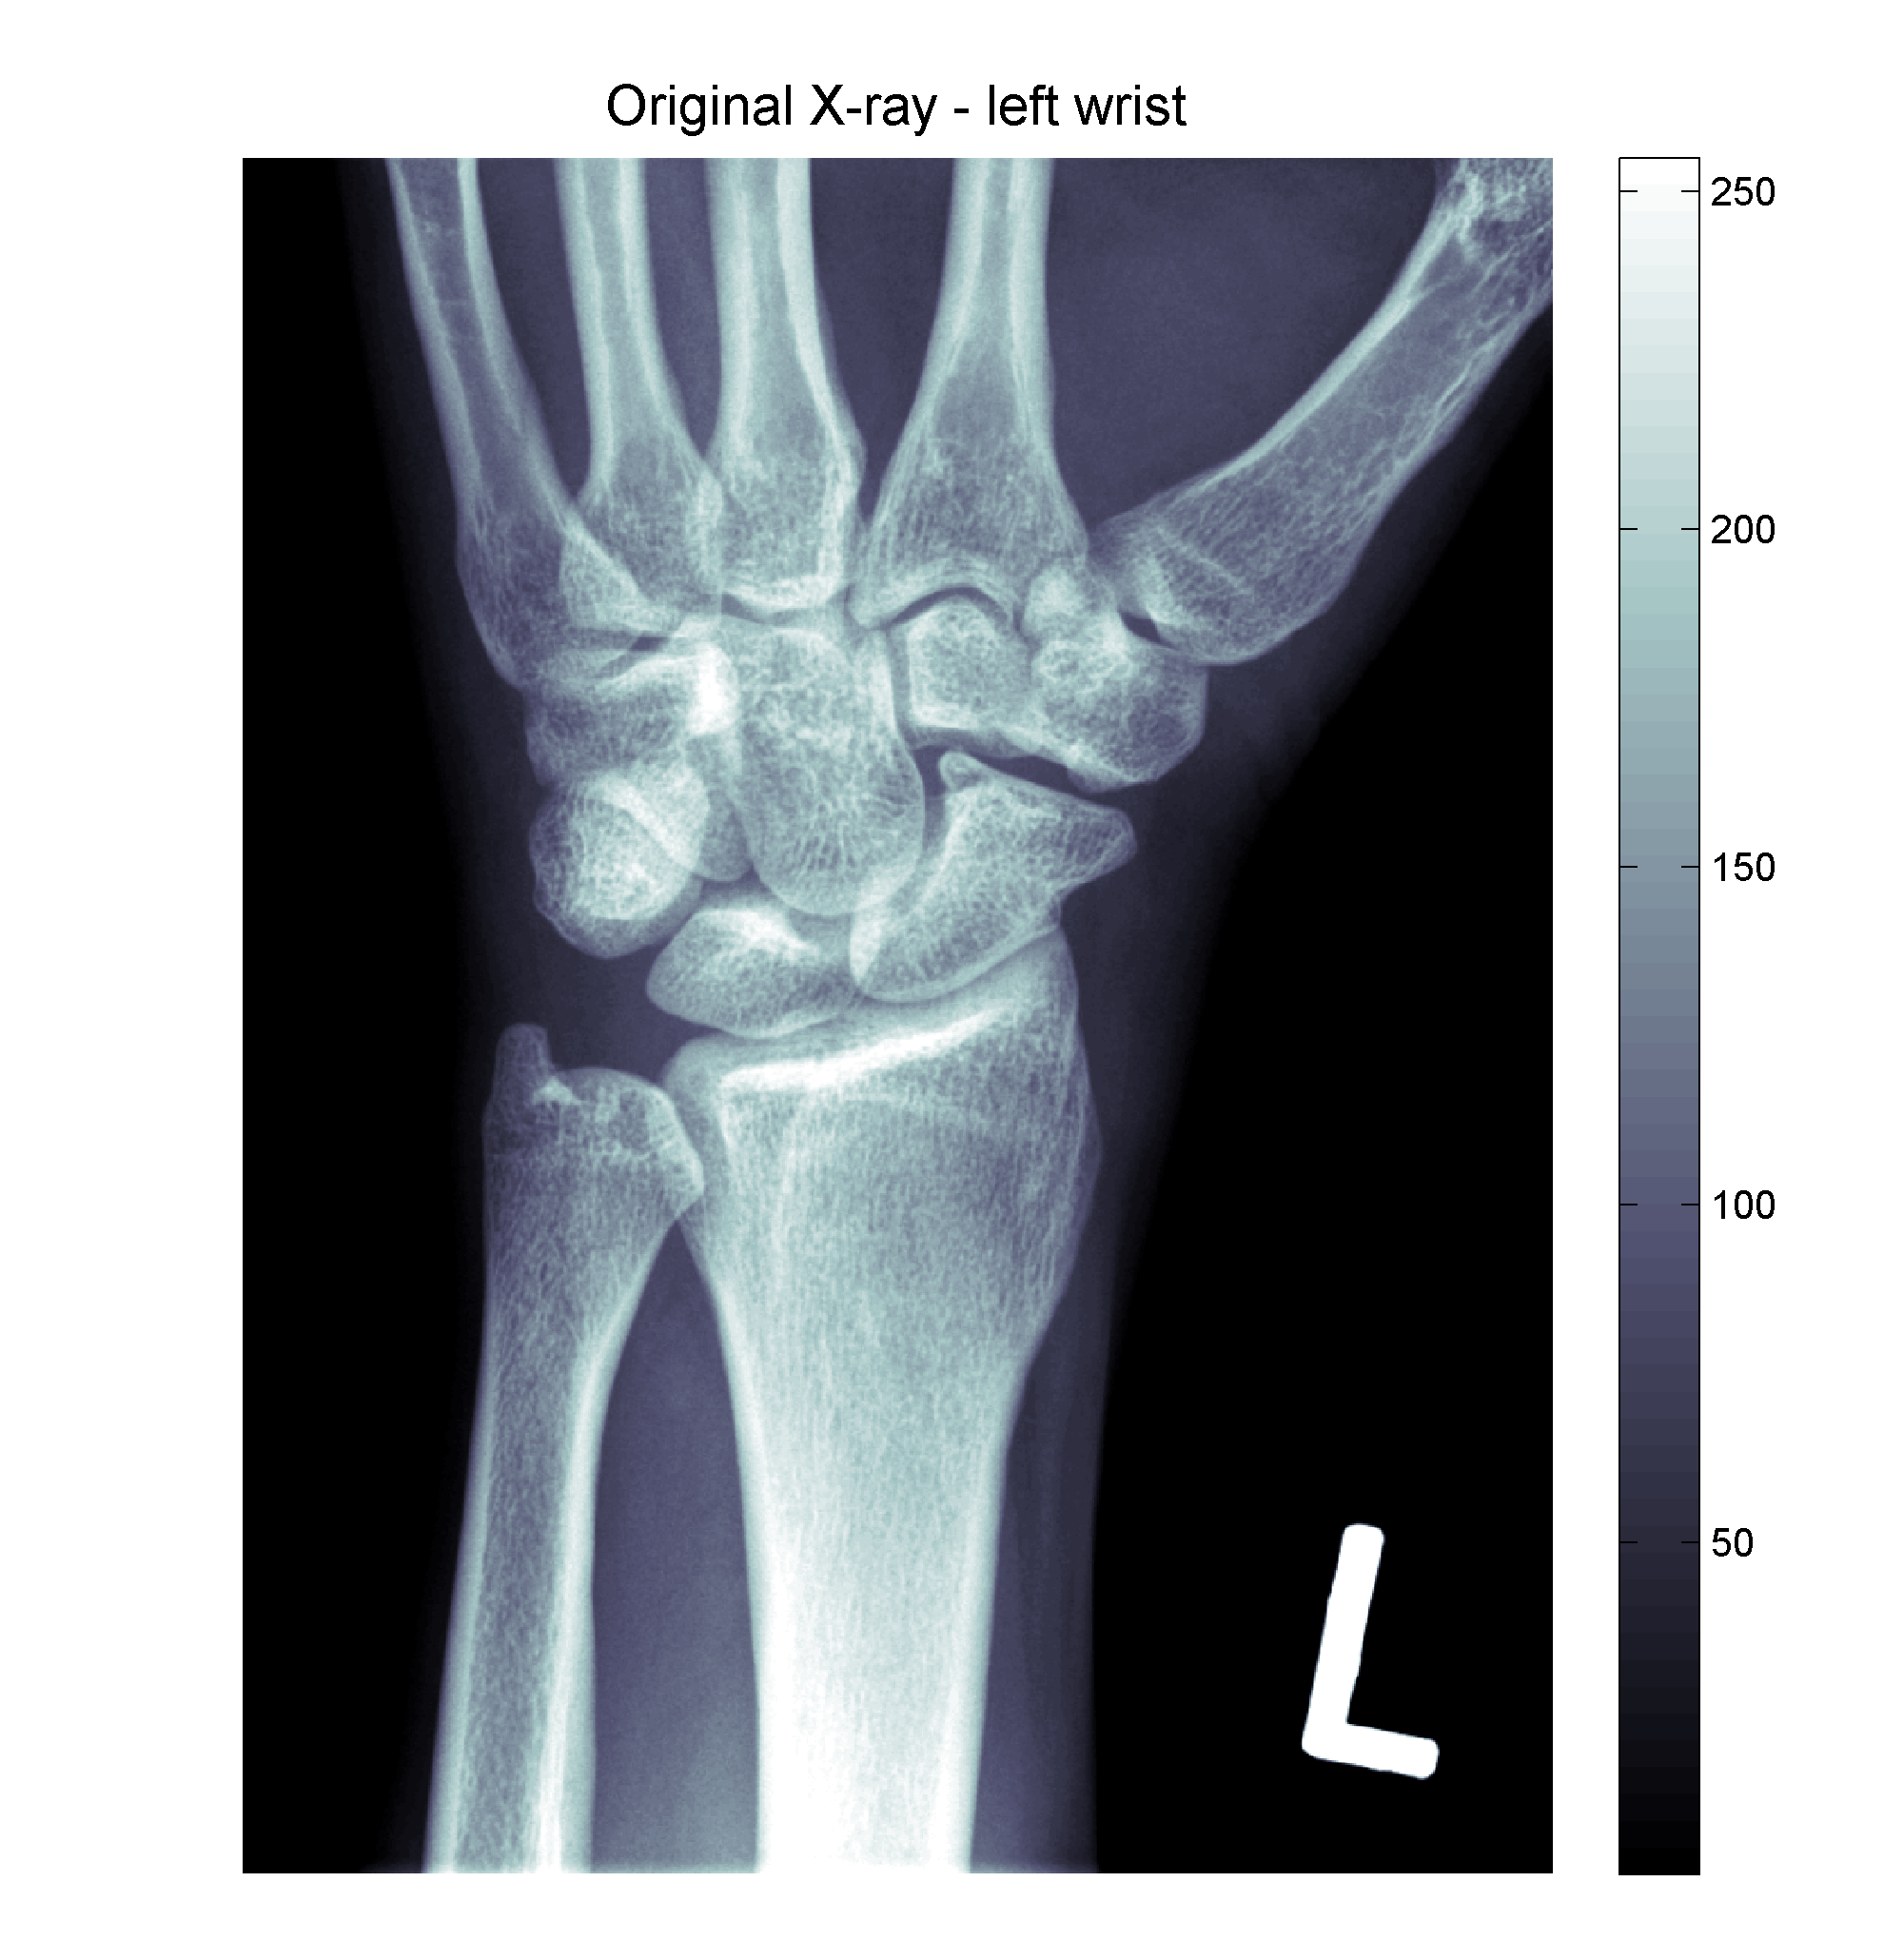

original Published October 21, 2011 at 2000 × 2060 in Lending you a hand with image processing – basic techniques 1 Share this: Email a link to a friend (Opens in new window) Email Share on LinkedIn (Opens in new window) LinkedIn Share on X (Opens in new window) X Share on Facebook (Opens in new window) Facebook More Print (Opens in new window) Print Share on Reddit (Opens in new window) Reddit Share on Tumblr (Opens in new window) Tumblr Like this:Like Loading...